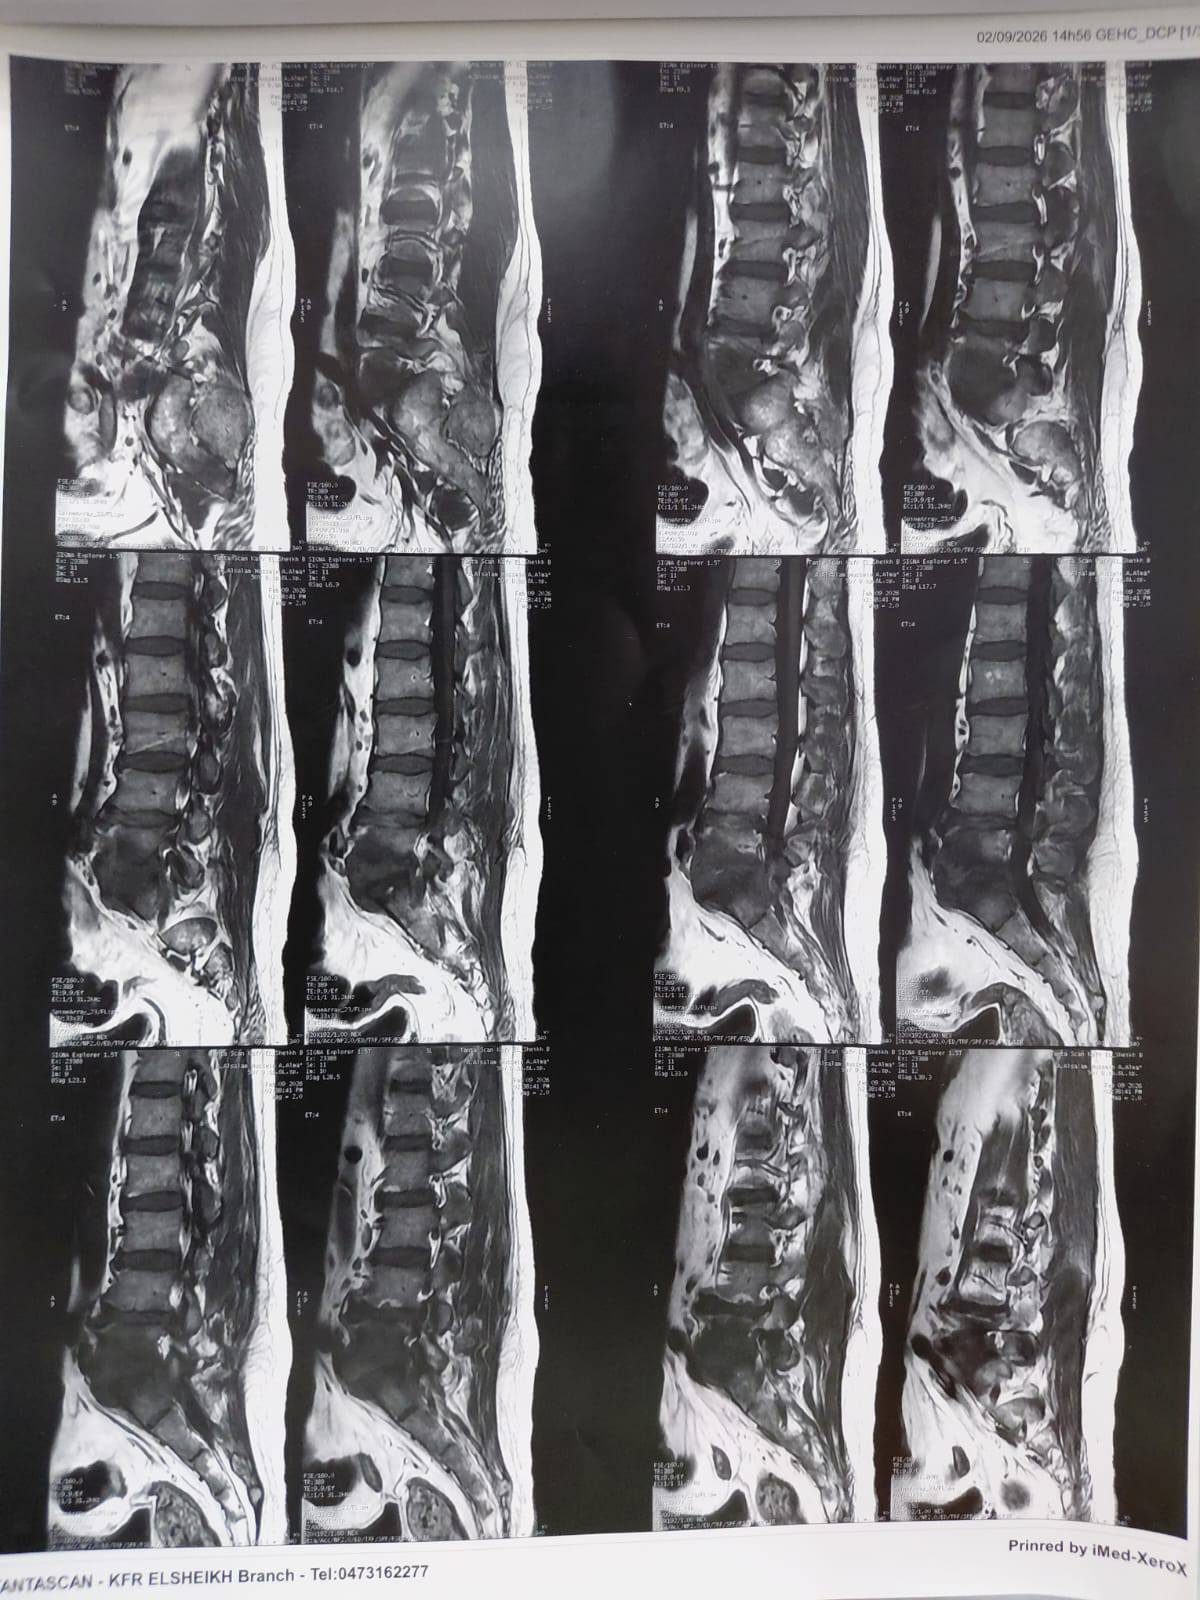

،أ.د/ جمال شمس مدير المستشفى الجامعي الرئيسي،أ.د/ حسام الدين جاد رئيس قسم جراحة العظام نجح فريق قسم جراحة العظام والكسور في إجراء عملية معقدة لالتهاب صديدي بالفقرات مسبب تآكل بالفقرات وضاغط على جذور الاعصاب الطرفية ومسبب ضعف بعضلات الطرفين السفليين مع التأثير على كافة جوانب الحياة للمريض .وقد تمكن الفريق من إزالة الالتهاب والصديد وتثبيت الفقرات وقسم جراحة العظام على أتم استعداد لاستقبال مثل هذه الحالات .